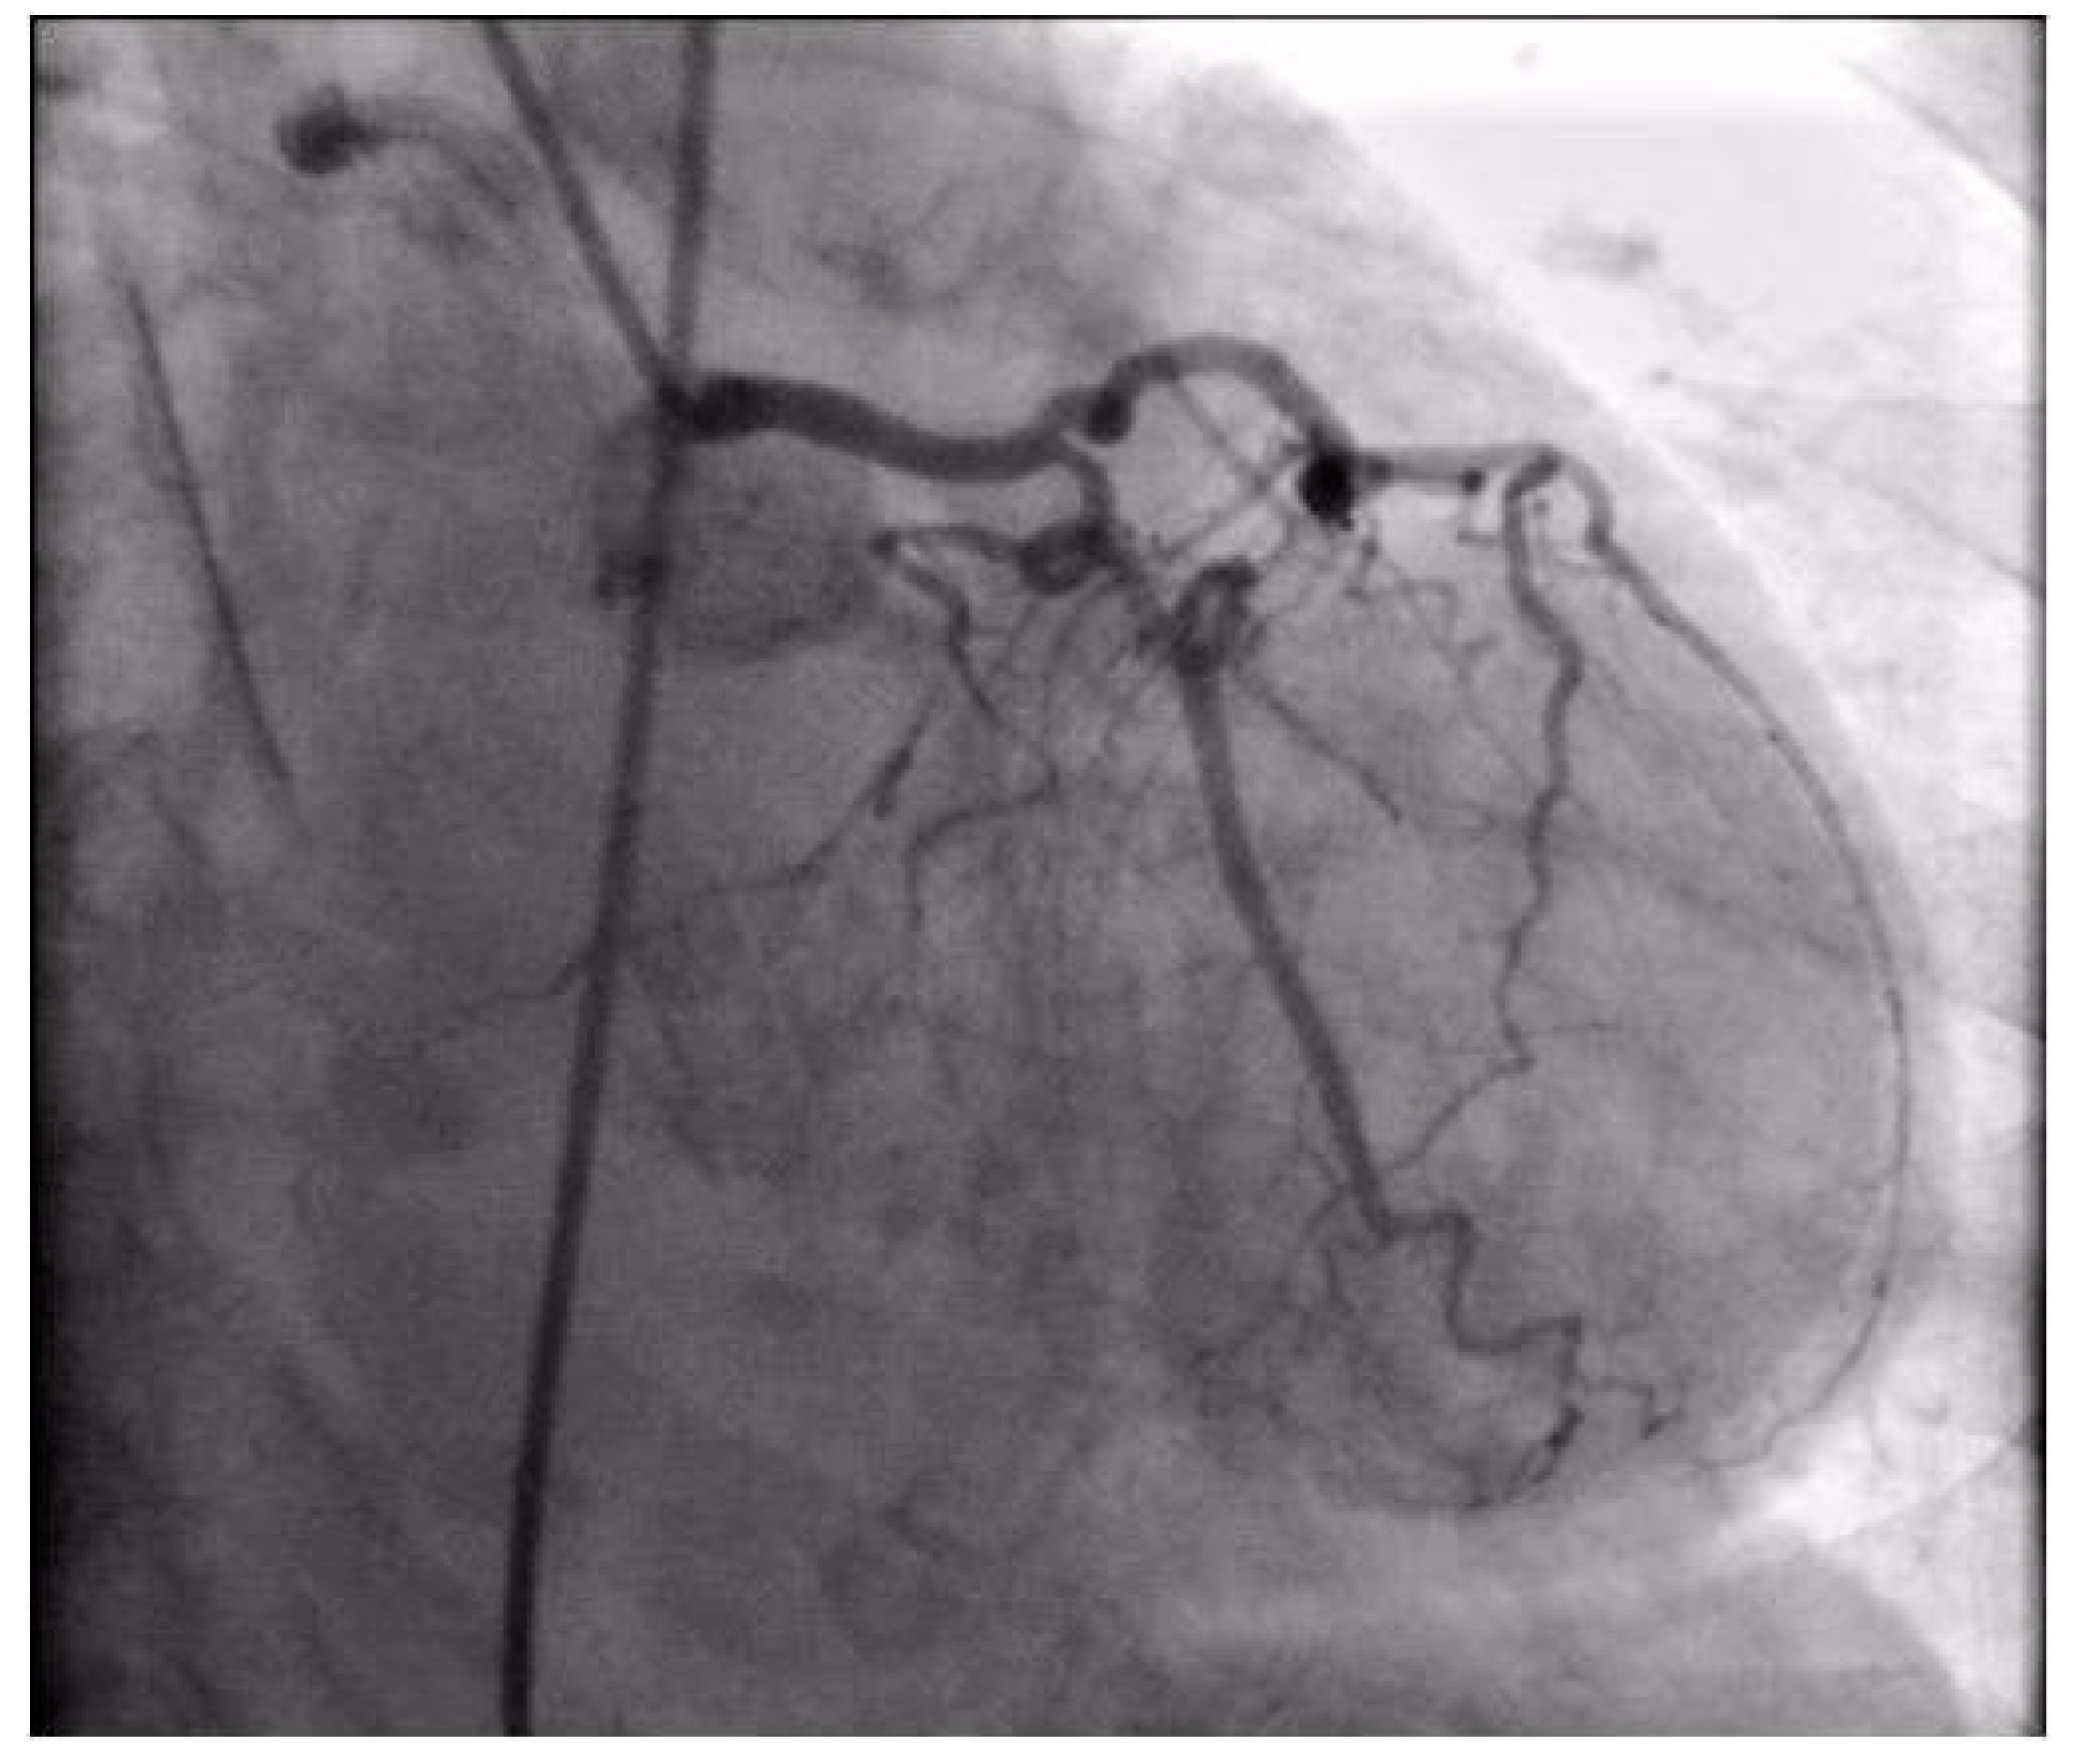

Coronary angiography was performed, showing the left coronary artery (LCA) was without significant lesions (Figure 6). On the right coronary artery (RCA), a subocclusive lesion was registered in the distal segment (Figure 7). Initially, it was thought to be a spasm, but the lesion persisted even after administering nitroglycerin intracoronary. Therefore, a primary percutaneous coronary intervention (pPCI) was performed with the implantation of a drug-eluting stent 16 × 25 mm (Boston Scientific, Marlborough, MA, USA) in the RCA, achieving the optimal result of the intervention (Figure 8).

Figure 6.

Coronary angiography registered left coronary artery without significant stenosis.